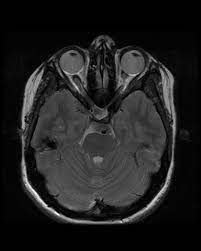

Humming Bird Sign Mickey Mouse Sign And Morning Glory Sign In Progressive Supranuclear Palsy Jalal Ma Menon Mk Menoufia Med J

Ultimate Radiology Hummingbird And Morning Glory Of Radiology